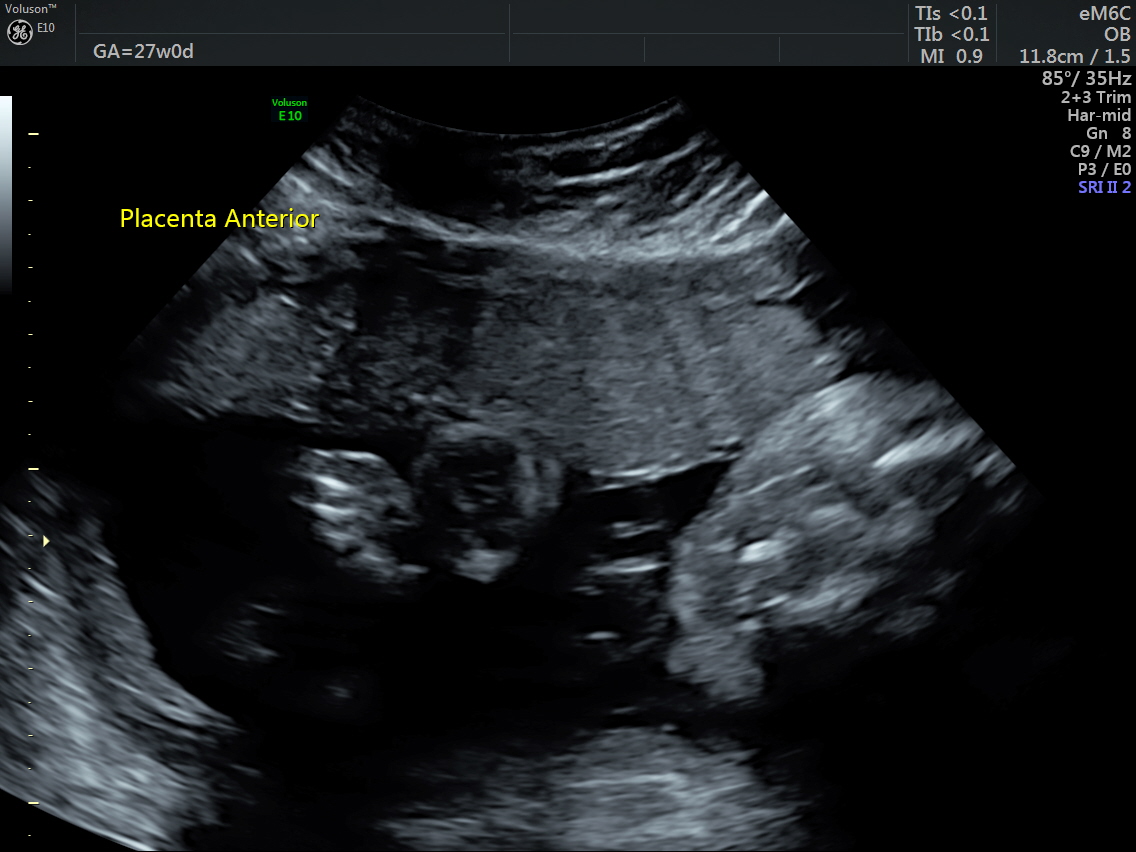

RT AORTIC ARCH_35 Published June 17, 2016 at 1136 × 852 in Rt aortic arch and aberrant left subclavian artery ← Previous Next →